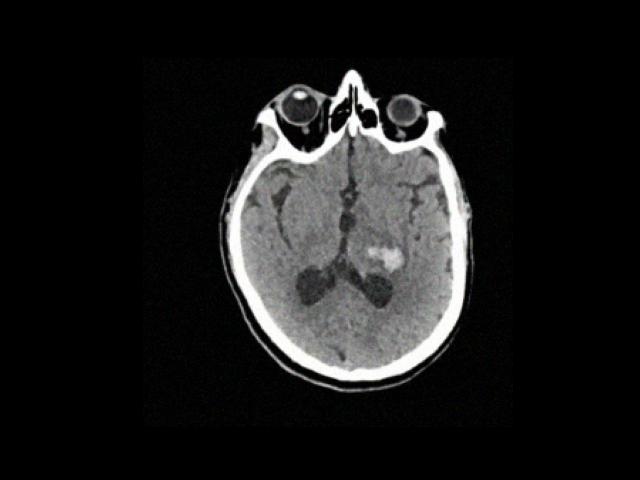

Sample Gallery